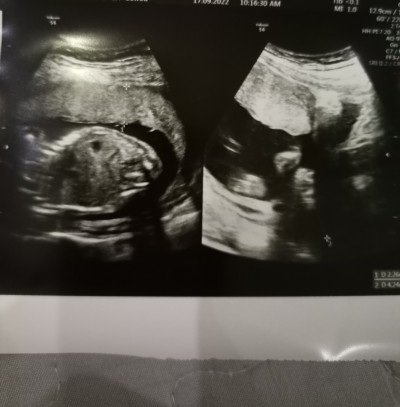

Bebeğin neresini göstermek istemiş acaba doktorumuz anlayamadım anlayan varmı ayrıntılı ultrasonda verilen sonucların bir tanesi

Sol foto bebegin govdesi hatta boynu görünüyor sağ foto bacak arasıni cekmeye çalışmış doktor iki çizgi var hatta orda bebek kız demek o.